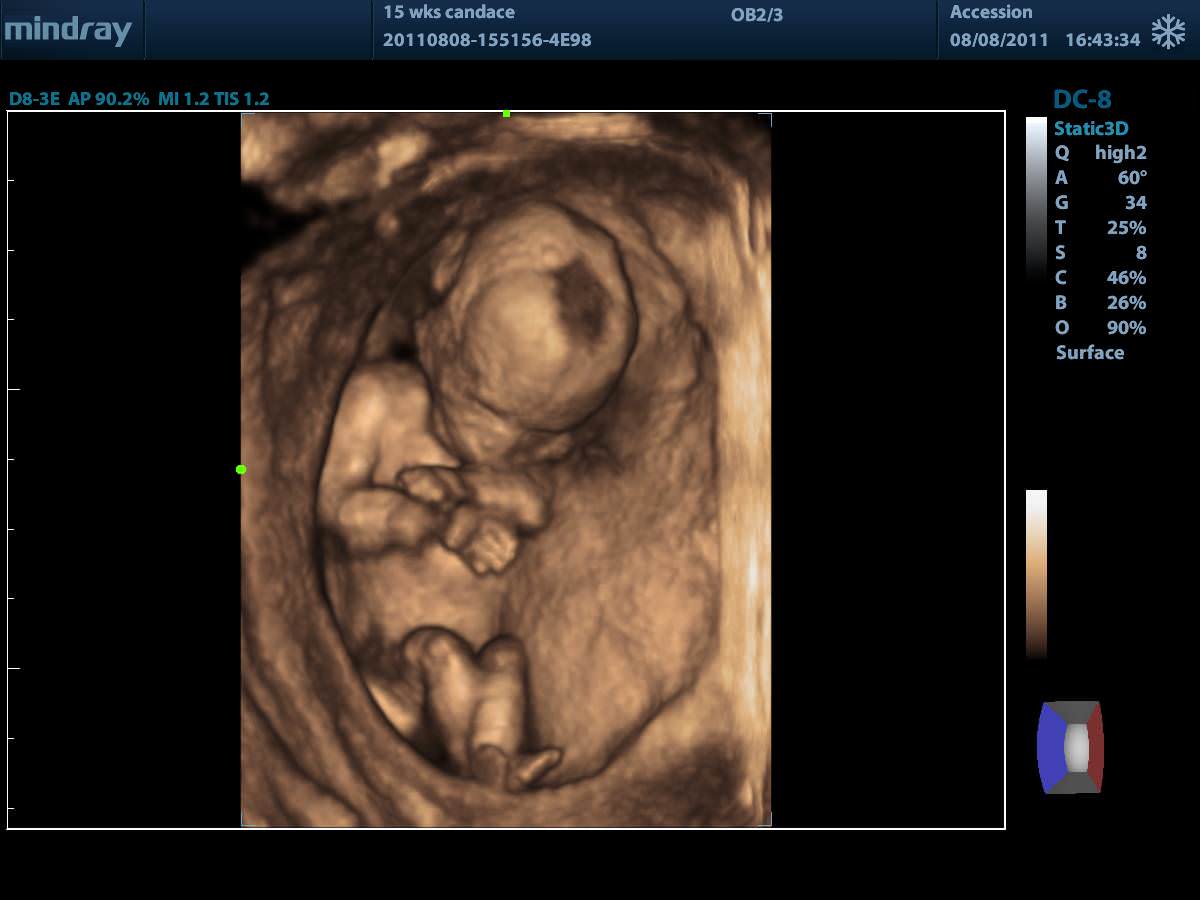

4D (трехмерное сканирование в реальном времени)

Режим Smart3D™ (технология 3-мерной реконструкции методом свободной руки)

- 4D Module. 4D Модуль для подключения объемных датчиков

- Smart OB. Программа автоматического измерения основных параметров биометрии плода в акушерстве

- iLive. Режим построения объемного изображения с применением технологии виртуальной свето-теневой обратоки с возможностью перемещения источник

- STICSTIC. Програмный модуль получения объемного изображения сердца плода с высоким временным и пространственным разрешением в серошкальном и ЦДК-р